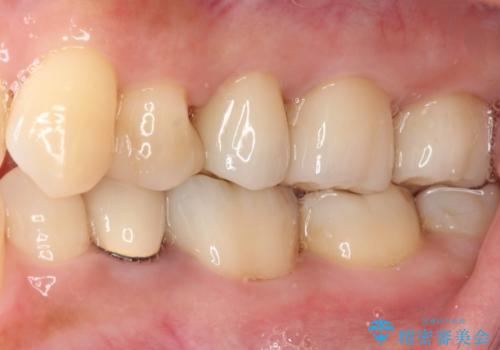

- 奥歯の銀歯をセラミックの白い歯にして、しみる症状も改善したいとのことで来院された患者様です。

知覚過敏の症状が強い歯と、銀歯の範囲や銀歯の下のむし歯が大きい歯は、インレー修復では対応が難しいためオールセラミッククラウンで、インレー修復で対応が可能な歯ではセラミックインレーにて修復することとしました。

知覚過敏の症状はなくなり、希望通りの白い歯になったと、患者様は大変満足されました。